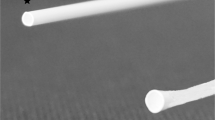

Schematic representation (a) and downsized visualization (b) of the circulation model: (1) replaceable section for the (c) vascular-phantom or the whole arterial tree, (2) filter for collecting thromboembolism, (3) warm water supply, (4) pneumatically driven pulsatile pump. The working fluid (3 L) consisted of a crystalloid solution (60% glucose solution). Depiction of the vacular phantom used for the evaluation of device/tissue interaction.

After extraction all vessels were examined sonographically within the circulation model. High grade stenosis (>50%) as well as occluded vessels and/or plaque ruptures were removed from the study. The extracted vessels had a standard length of 60 mm and a vessel diameter of 6.38 ± 3.17 mm. To fix and stabilize the thrombus position within the vascular phantom, a simple ligature of the extracted vessel was performed (standardized via Hegar probe) in central position of the extracted vessel (Fig. 1c). The Hegar probe defined a standardized residual lumen (5 mm) of the vascular phantom in order to guarantee both a stable thrombus position and an unhindered passage of the endovascular devices. Thrombus position and residual vascular lumen was verified sonographically under flow conditions.